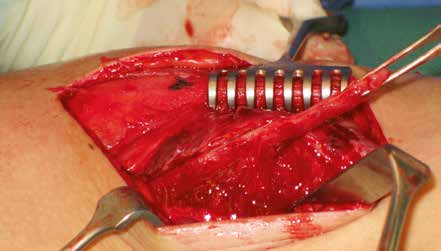

Hierzu zählen etwa frühzeitige Massage des Verletzungsgebietes, ungenügende Ruhigstellung sowie frühzeitiger Trainingsbeginn unter Nichtberücksichtigung der Schmerzen. Führen die Verknöcherungen zu Einschränkungen der Gelenkbeweglichkeit und Schmerzen oder zu starken Beeinträchtigungen der körperlichen Leistungsfähigkeit, können sie operativ entfernt werden (Abb. 2a u. b).

Der Eingriff sollte erst dann erfolgen, wenn die Entzündungsparameter und die alkalische Phosphatase rückläufig sind.